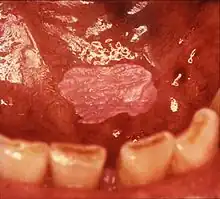

| Leukoplakia on the inside of the cheek. | |

Leukoplakia is a white patch on a inside of the mouth, which cannot be rubbed off.[8] It is associated with an increased risk of cancer.[4][5] The edges of the lesion are typically abrupt and the lesion changes with time.[4][6] Advanced forms may develop red patches.[6] There are generally no other symptoms.[9] It usually occurs within the mouth, although sometimes mucosa in other parts of the gastrointestinal tract, urinary tract, or genitals may be affected.[10][11][12]

Most cases of leukoplakia cause no symptoms,[9] but infrequently there may be discomfort or pain.[2] The exact appearance of the lesion is variable. Leukoplakia may be white, whitish yellow or grey.[28] The size can range from a small area to much larger lesions.[28] The most common sites affected are the buccal mucosa, the labial mucosa and the alveolar mucosa,[29] although any mucosal surface in the mouth may be involved.[2] The clinical appearance, including the surface texture and color, may be homogenous or non-homogenous (see: classification). Some signs are generally associated with a higher risk of cancerous changes (see: prognosis).